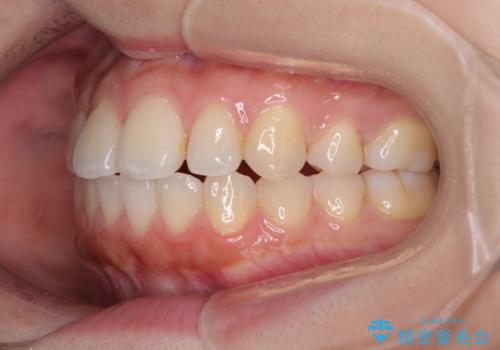

再矯正 開咬に後戻りした歯列をインビザラインで改善

- 矯正治療の後戻りを気にして来院された患者様です。

デコボコと上下前歯の隙間が気になるものの、しっかりと治療をしたいという意思はないとのことで、インビザラインの中でもアライナー数に制約のあるライトパッケージを用いて、治療できる範囲まで歯列を改善していくこととしました。

インビザラインは前歯部の開咬に効果的であることが多く、ライトパッケージにもかかわらず、十分満足のいく仕上がりとなりました。